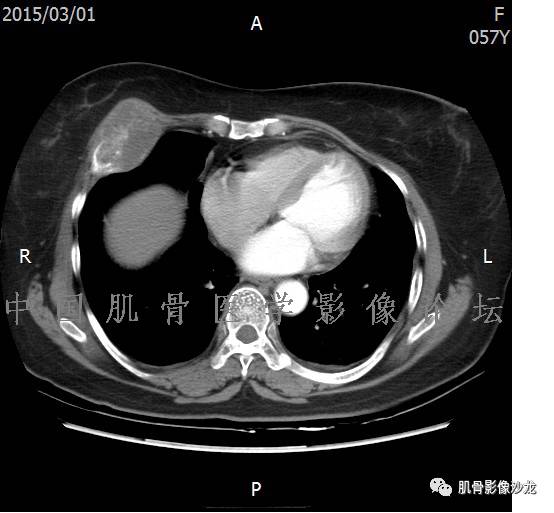

雪舞 :第二例,位于骶骨,有骨质破坏并有软组织肿块,软组织肿块边界清

雪舞: 第二例我们能够看到破坏与软组织肿块不成比例,软组织肿块大,破坏小

雪舞 :第二例挺难的,骨质破坏是溶骨性的,局部皮质中断,软组织肿块外缘光滑

医影在线 :无软骨钙化

飞鹰行动 :有的软骨肉瘤可以没有钙化

晴朗 :软骨基质不一定都是钙化的